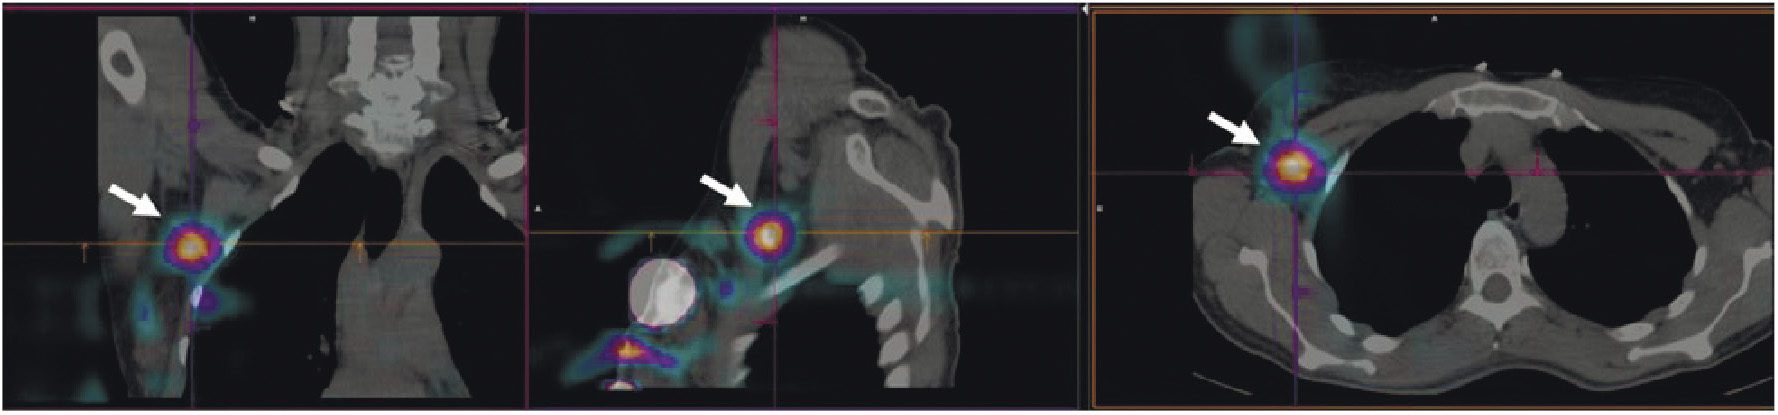

В НИИ онкологии Томского НИМЦ завершены первые фазы клинических исследований нескольких меченных технецием-99м каркасных белков (DARPin, ADAPT, Affibody), обладающих высокой аффинностью к рецептору эпидермального фактора роста второго типа (HER2/neu). Все препараты показали хорошую эффективность определения гиперэкспрессии рецептора HER2/neu при раке молочной железы и стадировании заболевания (рис. 1) [10, 11]. Кроме того, установлена возможность проведения ОФЭКТ/КТ с препаратами на базе скаффолдов для оценки эффекта терапии (рис. 2). Помимо основы РФЛП для диагностики злокачественных новообразований, каркасные белки могут служить вектором доставки при создании таргетных соединений для лечения злокачественных новообразований с гиперэкспрессией рецептора HER2/neu [13].

Рис. 1. ПЭТ-изображение пациентки с HER2/neu-позитивным раком молочной железы, выполненное через 5 суток после введения 89Zr-транстузумаба (a), стрелками обозначены метастазы в печень и кости [12]; ОФЭКТ-изображение пациентки с HER2/neu-позитивным раком молочной железы через 2 ч после введения 99mTc-ADAPT6 (б), стрелками обозначены первичная опухоль, метастазы в лимфатические узлы, печень и кости

Рис. 2. ОФЭКТ/КТ-изображение пациентки с HER2/neu-позитивным раком правой молочной железы до начала лечения, выполненное через 2 ч после введения 99mTc-DARPIN-G3 (а), стрелками обозначены первичная опухоль (SUVmax = 3.1), метастазы в лимфатические узлы (SUVmax = 8.8) и кости; ОФЭКТ/КТ-изображение той же пациентки после двух курсов терапии транстузумабом через 2 ч после введения 99mTc-DARPIN-G3 (б), стрелками обозначена первичная опухоль (SUVmax = 0.55), метастазы не визуализируются